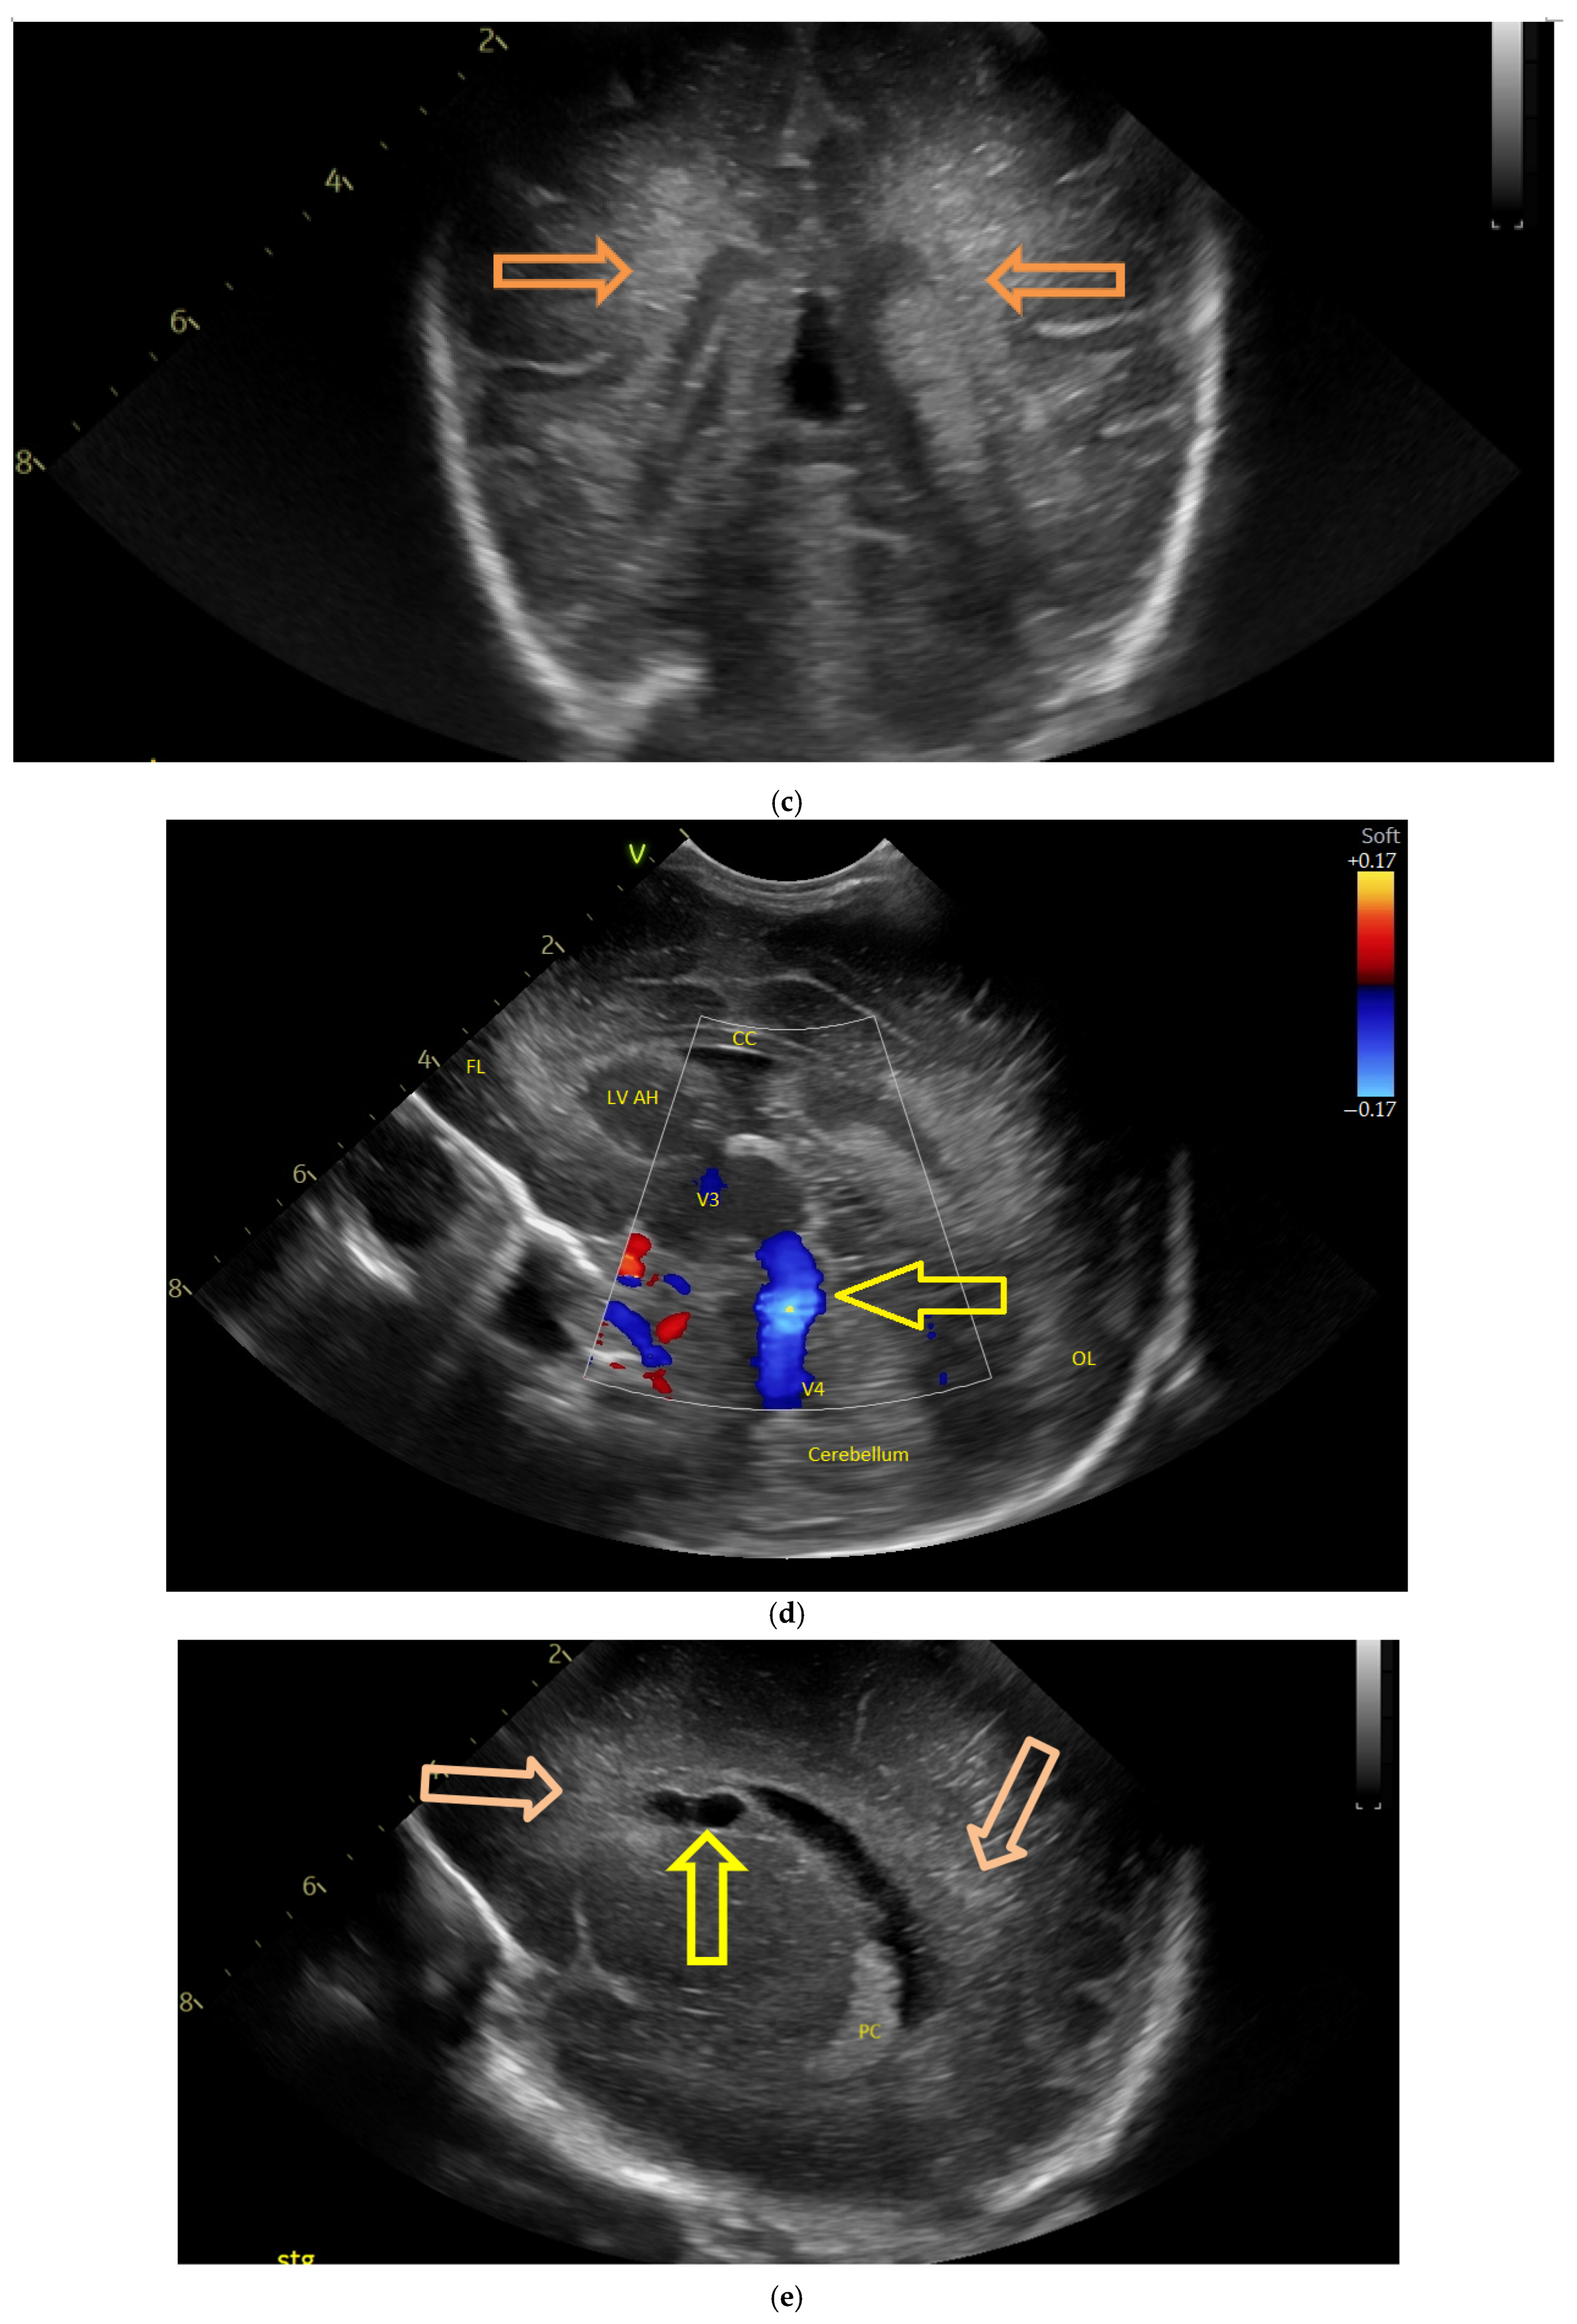

(a) Cranial ultrasound. Coronal view. Lateral ventricles and third ventricle enlargement. L1, L2—Levine index measurement. L3, L4—posterior horn of the lateral ventricles’ width measurement. L5—third ventricle width measurement (personal image collection). (b) Cranial ultrasound. Sagittal view. Enlarged third and fourth ventricles. L1, L2—third ventricle measurements. L3, L4—fourth ventricle measurements (personal image collection). (c) Cranial ultrasound. Sagittal view. Enlarged lateral ventricles. Up—left ventricle. Down—right ventricle (personal image collection). (d) Cranial ultrasound. Coronal view. Punctuate hyperechoic images were observed in the right lobe (personal image collection). (e). Up left—MRI T1 sequence. Up right—MRI T2 sequence—susceptibility weight imaging (SWI). Down—CT scan. Transversal view. Yellow arrows—multiple calcifications can be seen in the CT scan (personal image collection). (f) Cranial ultrasound. Coronal view. Lateral ventricles. L1, L2—Levine index measurement. L3, L4—anterior horn width measurement. Blue arrow—intraventricular shunt (personal image collection). (g) Cranial ultrasound. Sagittal view. Thalamo-occipital distance measurements. Up—right ventricle. Down—left ventricle (personal image collection).

At six weeks after birth, an MRI scan was performed, while a CT scan was performed at 14 weeks of life, both providing valuable information regarding the sequelae of Toxoplasmosis (Figure 4e). Even though a few signs were observed on the MRI, the CT scan better outlined the presence of the parenchymal calcifications. A neurosurgical intervention was intended, a ventricle puncture was performed, and a shunt was placed in the right ventricle. The cranial ultrasound at two months of life did not show notable improvements, however (Figure 4f,g). The neurological examinations showed axial hypotonia and limb hypertonia.

(a,b) MRI—T2 sequence. Sagittal view. Antenatal. Yellow arrows indicate the place of the suspected tumor (personal image collection). (c) Cranial ultrasound. Sagittal view. Up—enlarged left ventricle. D1—thamalo-occipital distance. Down—enlarged right ventricle. D1—thalamo-occipital distance (personal image collection). (d) Cranial ultrasound. Sagittal view. Enlarged third ventricle. Fourth ventricle is normal. D1, D2—measurements of the third ventricle (personal image collection). (e) Cranial ultrasound. Transtemporal view. Enlarged third ventricle. Sylvian aqueduct is not visible. D1—measurement of third ventricle. LV AH—lateral ventricle anterior horn. LV OH—lateral ventricle occipital horn. V 3—third ventricle (personal image collection).

After stabilization, the cranial ultrasound exam revealed enlargement of the lateral ventricles and third ventricle, with a normal fourth ventricle. There was no visualization of the Sylvian aqueduct, which raised the suspicion of aqueduct atresia or stenosis (Figure 5c–e). There was no improvement seen in the cranial ultrasound examinations that followed.